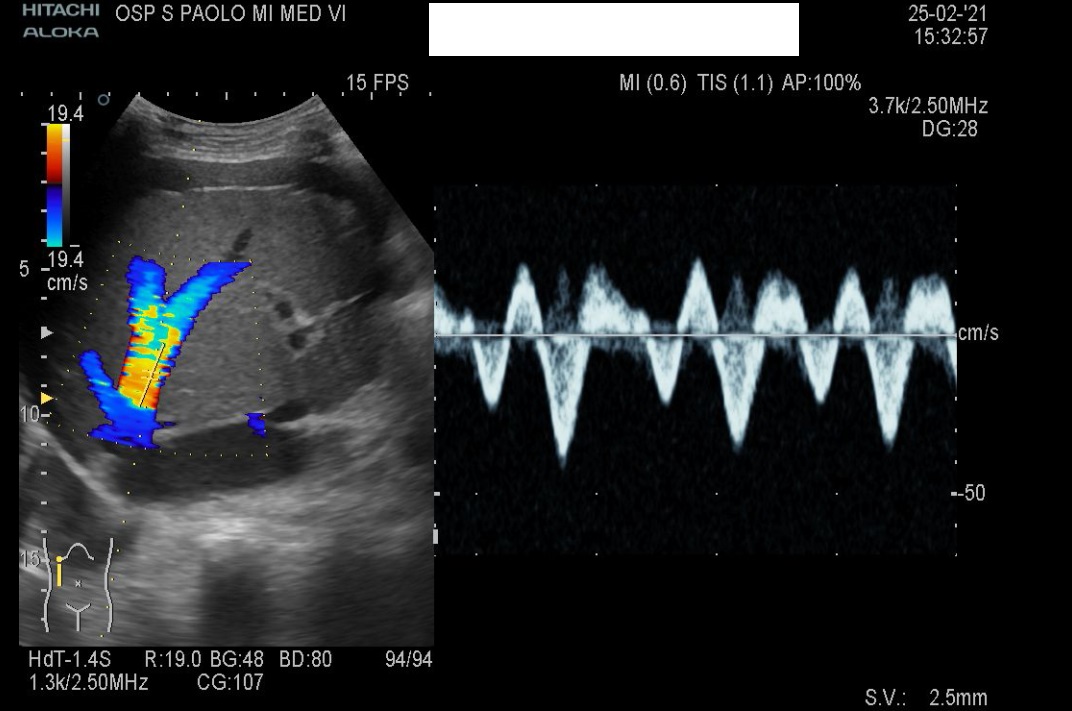

Pulsatile portal venous flow. This likely takes place because the pressure has to transmit across the hepatic sinusoids, which buffer the hepatic venous pressure. Eventually, the portal venous flow pattern changes, going from a monophasic signal to a pulsatile one.